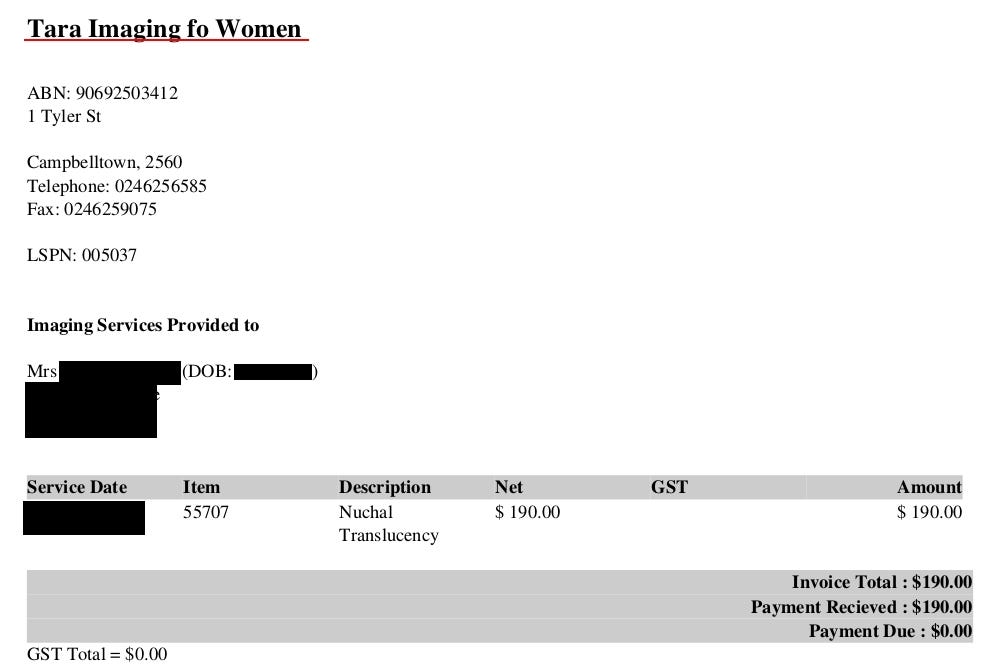

First of the exposed server belongs to Tara Imaging for Women (http://www.taraimaging.com.au/)

To confirm the assumption, I downloaded one invoice:

Payments and debtors details go back even to 2009 and photos to 2016. Probably there are some rules that require to keep medical data for specific period of time.